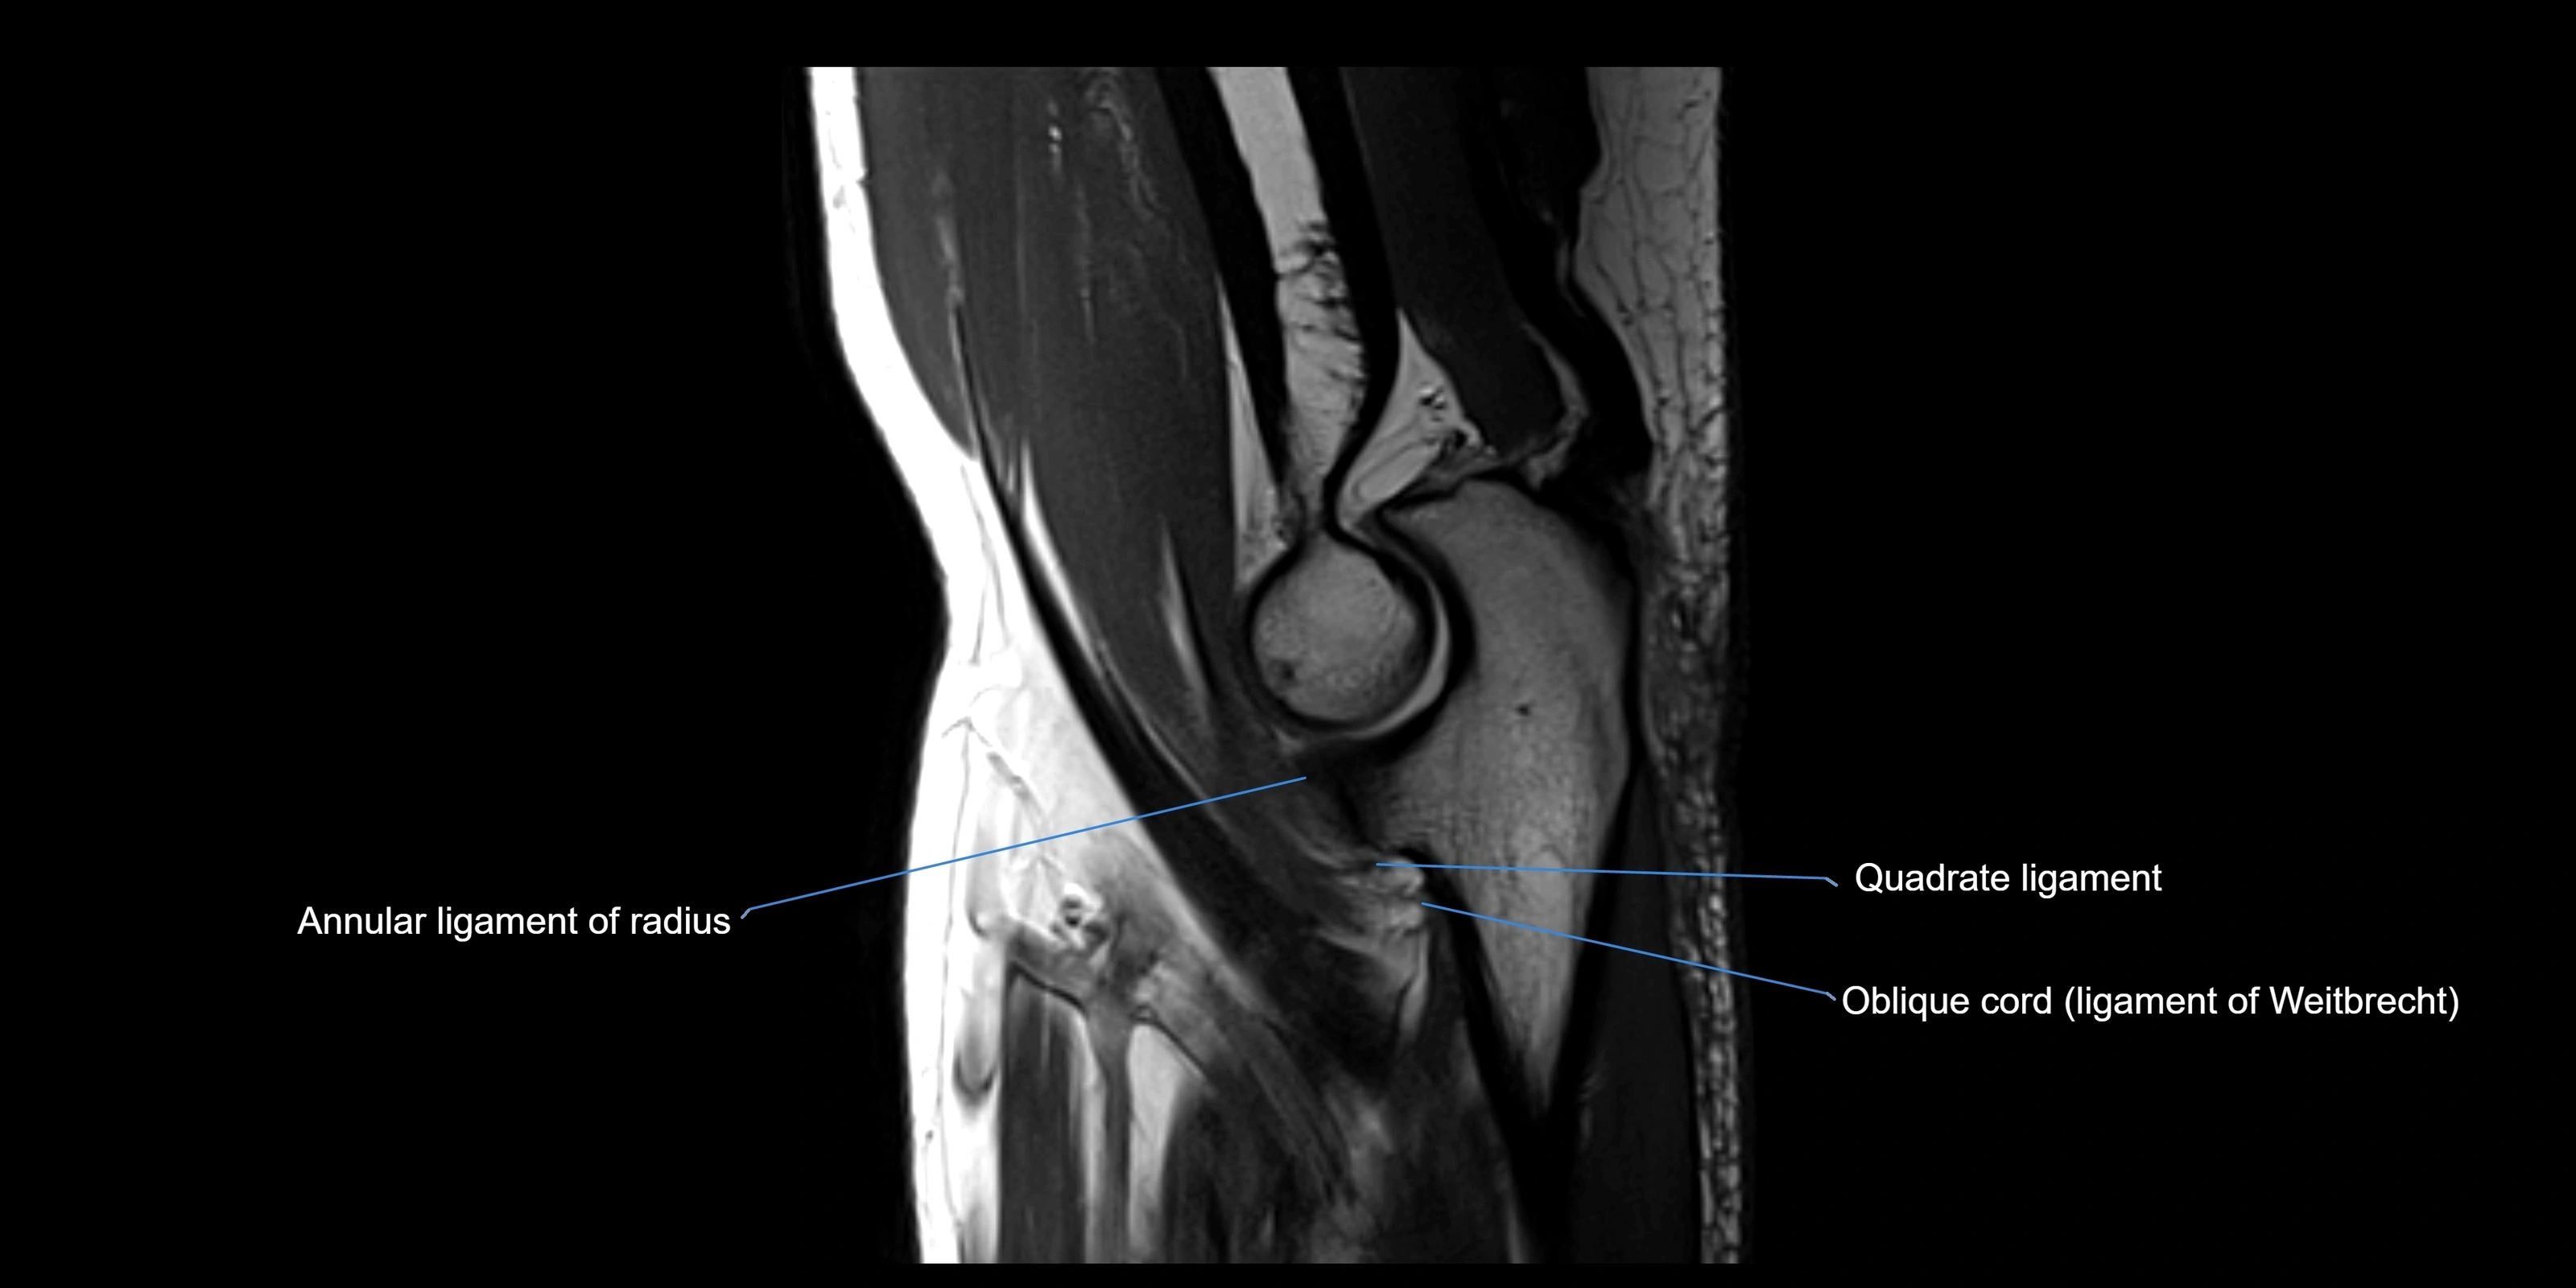

Annular ligament of radius

The annular ligament of the radius is a strong, circular band of fibers that encircles the head and neck of the radius, holding it securely against the radial notch of the ulna. It forms part of the proximal radioulnar joint, permitting smooth rotation of the radius during pronation and supination of the forearm.

The ligament acts like a collar or loop, maintaining radial head stability while allowing rotation. It is essential for forearm motion, elbow stability, and load transmission from the radius to the ulna and humerus.

Origin, Course, and Insertion

• Origin: Arises from the anterior margin of the radial notch of the ulna.

• Course: Forms a strong circular band that wraps around the radial head and neck, maintaining them within the radial notch.

• Insertion: Attaches to the posterior margin of the radial notch, completing a fibrous ring around the radial head.

• The inner surface of the ligament is lined with synovial membrane, allowing frictionless rotation.

Relations

• Superiorly: Blends with the capsule of the elbow joint.

• Inferiorly: Supported by the quadrate ligament at the neck of the radius.

• Medially: Attached to the ulnar radial notch.

• Laterally: In contact with the radial head and its articular cartilage.

• Anteriorly: Related to the radial collateral ligament of the elbow.

• Posteriorly: Continuous with the elbow joint capsule.

MRI Appearance

T1-weighted images:

• Ligament: low signal intensity (dark), appearing as a continuous band around the radial head.

• Adjacent fat and marrow: bright, creating contrast with the ligament.

• Thickening or disruption indicates injury or fibrosis.

• Joint capsule and synovium seen as thin low-signal lines contiguous with ligament margins.

T2-weighted images:

• Ligament: low signal (dark) with clear delineation from joint fluid.

• Fluid or edema: bright hyperintense, separating or surrounding the ligament in partial tears.

• Complete tear: discontinuity or non-visualization of ligament fibers, often with joint effusion.